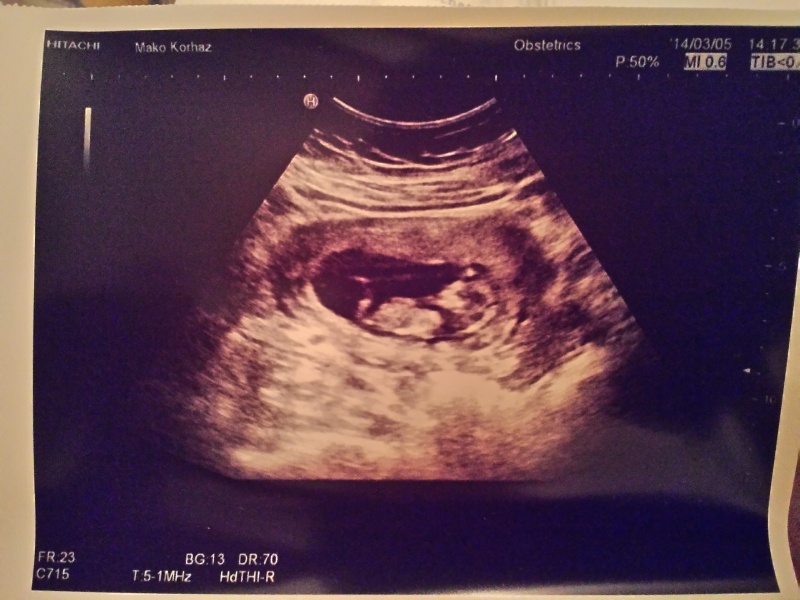

GereGabi, remélem most megjelenik a vonalzóm